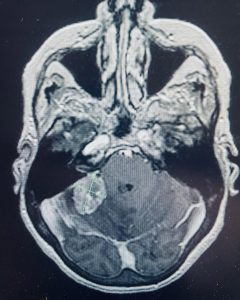

This female patient presented with dizziness and difficulty walking with a past history of colon cancer. Her brain MRI showed a metastatic tumor deep in her cerebellum. The pressure on the cerebellum was causing her balance issues. She had a craniotomy to remove the tumor. Microsurgery and stereotactic navigation were useful in this case given the tumor’s location deep in the brain. The tumor was completely removed (second picture, arrows), and her neurologic difficulties all resolved.